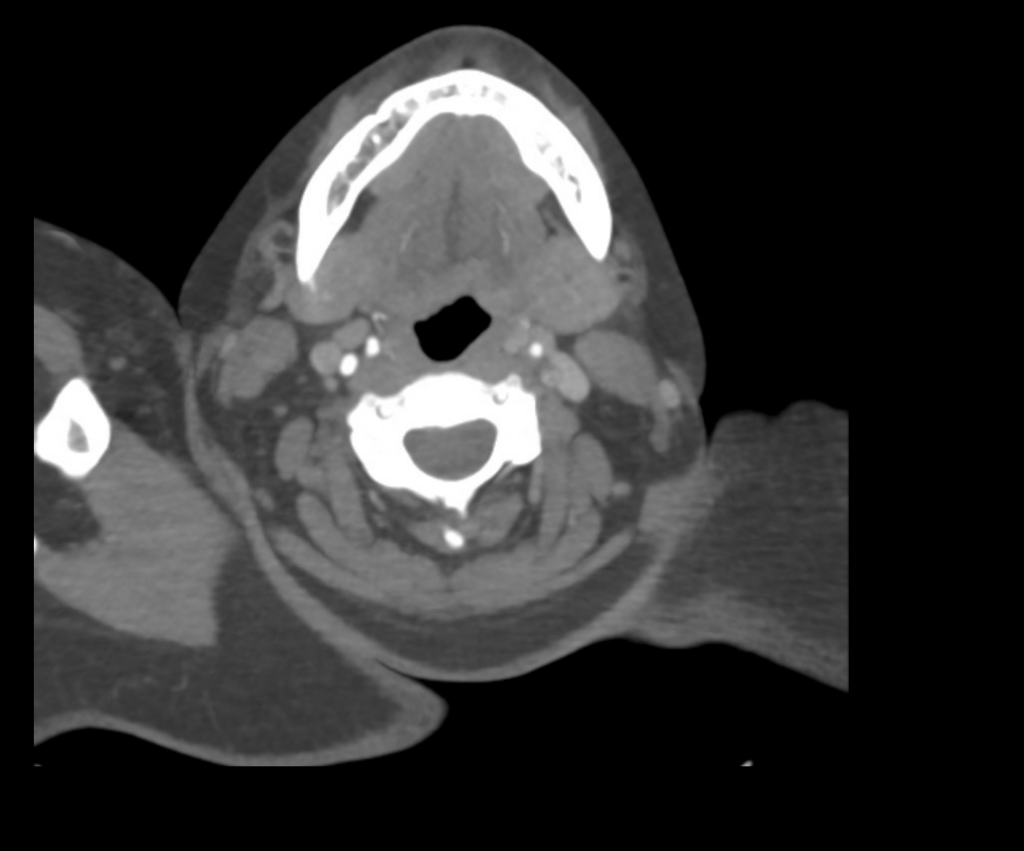

Vengono eseguiti una TAC cerebrale, un angiogramma e una scansione della perfusione cerebrale.